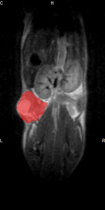

ヒト ME180 頸がん細胞の植込みから7週間後に撮像を実施しました。

T2 強調: 高速スピンエコー FSE、TE/TR=52.7/3500、

FOV=50x28mm、Matrix=256x144、NEX=8、ETL=16、

分解能:195um、取得時間:5分08秒

●T2強調画像:

後肢筋からの腫瘍境界線を鮮明に定義可能です。その為、T2強調画像を用いることによって、腫瘍容積を簡便に定量することができます。(腫瘍容積 = 156mm3)